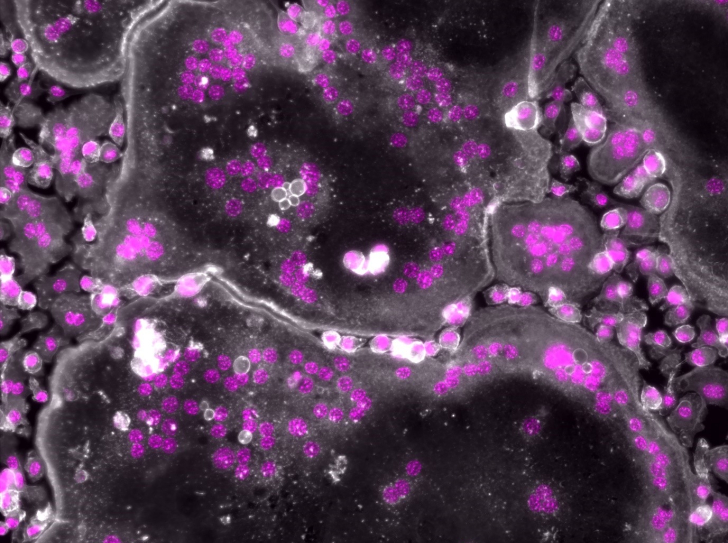

Découverte d’un nouveau mécanisme clé de la progression des maladies rénales

Les maladies rénales chroniques ont un point commun : une fois amorcées, quelle qu’en soit la cause et même si celle-ci est traitée, elles finissent…